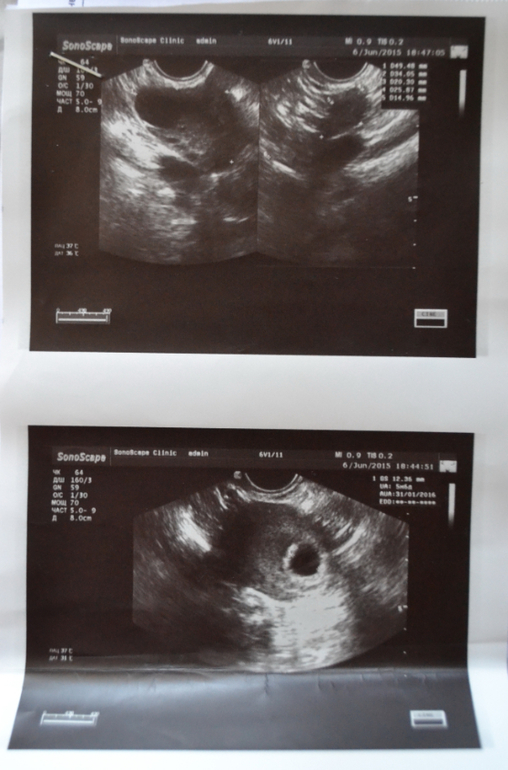

в 5+6 недель сходили с мужем на узи,там нам рассказали,что беременность маточная,но поставили угрозу,сказали есть гематома и отслойка плаценты небольшого размера.

вчера сделала узи в Диагностическом центре на кондратюка(там ведет прием моя гинеколог Саламатина Е.С.,у классной узистки Данчук Е.А.)

По результатам :беременность прогрессирующая,без угроз,все идеально,плод есть,сердцебиение тоже)) Саламатина сказала оставить только фольку)